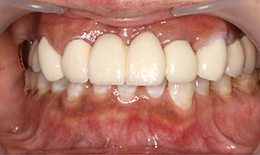

インプラント症例(23) 60歳 女性

- 保存困難な歯を抜歯後、インプラントを5本埋め込んで、セラミックスクラウンを被せた

- インプラントを2本埋め込んで、セラミックスクラウンを被せた